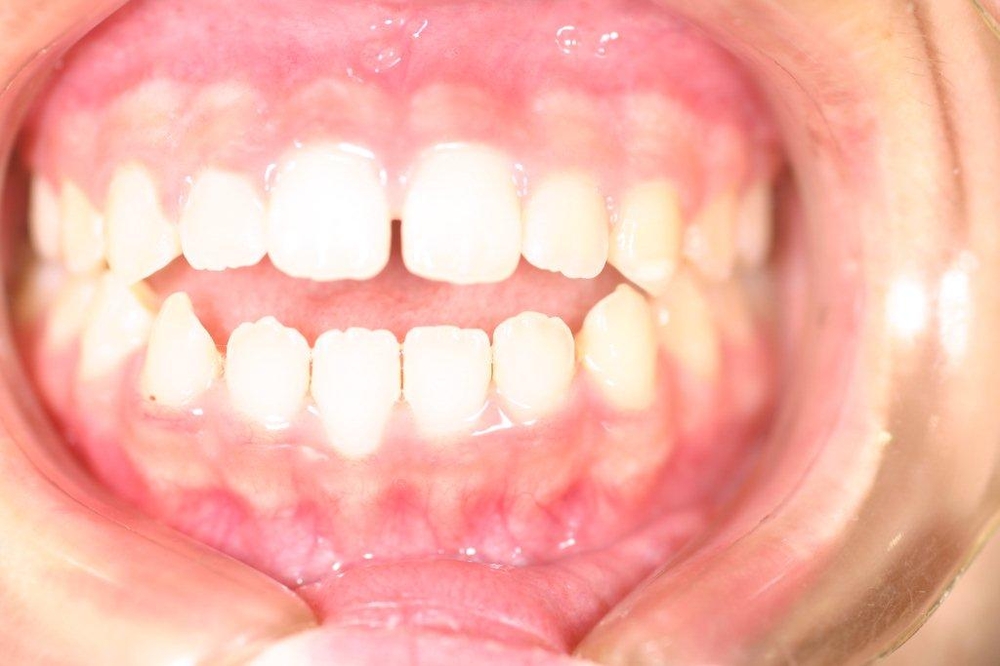

上顎の中央の歯一本が前にとびだしている治療例

Before

After

上顎の中央の歯一本が前にとびだしている症例です。これだけ前に出ていると、歯を抜いて並べていくか、何本かの歯を削らないときれいに並べられません。

このケースは、上の顎に矯正用のミニスクリュー{矯正用ミニインプラント}を入れて、歯を抜かず、削りもしないで、しかも上顎だけの矯正で治した症例です。

矯正用インプラントを使うことによって歯並び全体を後方に動かすことができるようになったため、このような治療ができるようになりました。

年齢 20代

治療期間 8ヶ月

治療費用 800,000円

治療のリスク 特になし